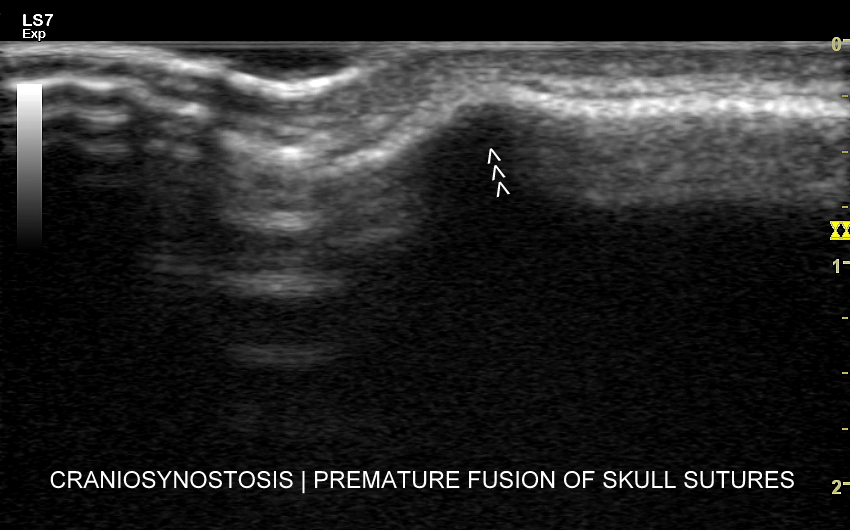

USG główki z oceną szwów i powłok

Poza strukturami wewnątrzczaszkowymi w badaniu USG główki niemowlaka oceniana jest pokrywa czaszki, w tym szwy i kości czaszkowe, tkanka podskórna oraz skóra głowy. Badanie USG szwów czaszkowych ma istotne znaczenie przy ocenie niesymetrycznego lub zdeformowanego kształtu głowy w kontekście rozpoznania kraniosynostozy (ang. craniosynostosis), tj. stanu, w którym dochodzi do przedwczesnego oraz nieprawidłowego zarastania szwów. W kraniosynostozie w miejscu zarastania tworzy się zwykle patologiczne twarde uwypuklenie / guz, które posiada charakterystyczny obraz sonograficzny pozwalający na rozróżnienie zarastania szwów w przebiegu kraniosynostozy od przedawkowania witaminy D, czy fizjologicznej wcześniejszej fuzji kości czaszki.

Patologiczne zarastanie szwów może być symetryczne lub niesymetryczne oraz dotyczyć jednego lub więcej szwów. W zależności od tejże konstelacji czaszka może przyjmować różnorodne formy deformacji w postaci scaphocefalii (syn. dolichocephalia, czaszka łódkowata / wydłużona w przebiegu zarośnięcia szwu strzałkowego), brachycefalii (krótkogłowie w przebiegu zarośnięcia obu szwów wieńcowych)trigonocefalii (trójkątnogłowie w przebiegu zarośnięcia szwu czołowego), plagiocefalii przedniej lub tylnej (skośnogłowie w przebiegu zarośnięcia jednego ze szwów wieńcowego lub węgłowego), turricefalii (syn. oxycefalia, czaszka wieżowata w przebiegu zarośnięcia szwów wieńcowych i któregoś z pozostałych), mikrocefalii (mała czaszka w przebiegu zarośnięcia wszystkich szwów) lub czaszki w kształcie liścia koniczyny (niem. kleeblattschädel). Sprawna diagnostyka deformacji czaszki ma wielkie znaczenie. Otóż kraniosynostoza jest potencjalnie niebezpieczna dla zdrowia, a nawet życia dziecka, a zwykle leczy się ją chirurgicznie. Z kolei częściej występująca łagodna deformacja w postaci plagiocefalii ułożeniowej wywołana jest zwykle tendencją do leżenia dziecka na wznak z główką skierowaną w jedną stronę, zwykle prawą; jest ona problemem bardziej estetycznymi aniżeli medycznym, a leczy się ją przy pomocy kasku oraz zaleceń rehabilitacyjnych.